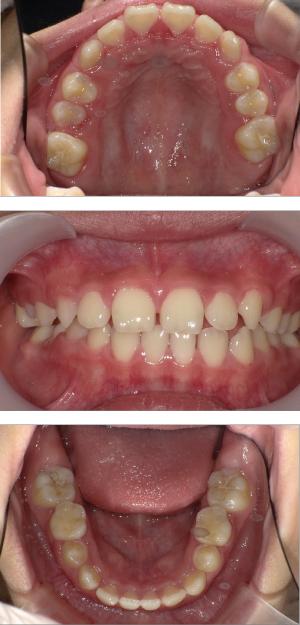

- 歯並びの改善

矯正治療は大人になって始めるよりも子どもの頃から始めた方が確実に良い結果をもたらします。成長が盛んな子供の時期に、顎や顔の成長を利用しながら治療ができる大きなメリットがあるからです。当院では、非抜歯矯正を推奨しておりバイオブロック矯正を取り入れています。

バイオブロック矯正の考え方は歯並びが悪くなる原因にアプローチする治療法になります。

舌の位置や口呼吸から乱れてしまった下顎の後退を正し、顎顔面が本来あるべき位置へと誘導させていく治療です。